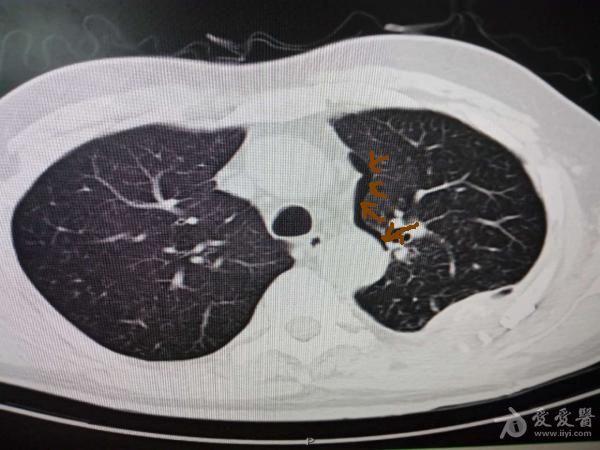

患者出院 由于患者咳嗽剧烈导致肺泡破裂空气沿肺血管周围进入纵隔

图片尺寸600x450